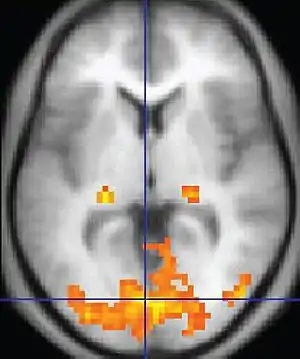

| Ressonância Magnética Funcional (fMRI) | Imagem dependente do nível de oxigênio no sangue | BOLD | Mudanças na magnetização dependente da saturação de oxigênio da hemoglobina refletem a atividade tecidual.[84] | Localização da atividade cerebral ao executar uma tarefa atribuída (por exemplo, falar, mover os dedos) antes da cirurgia, também usado na pesquisa de cognição.[85] | ![]() |